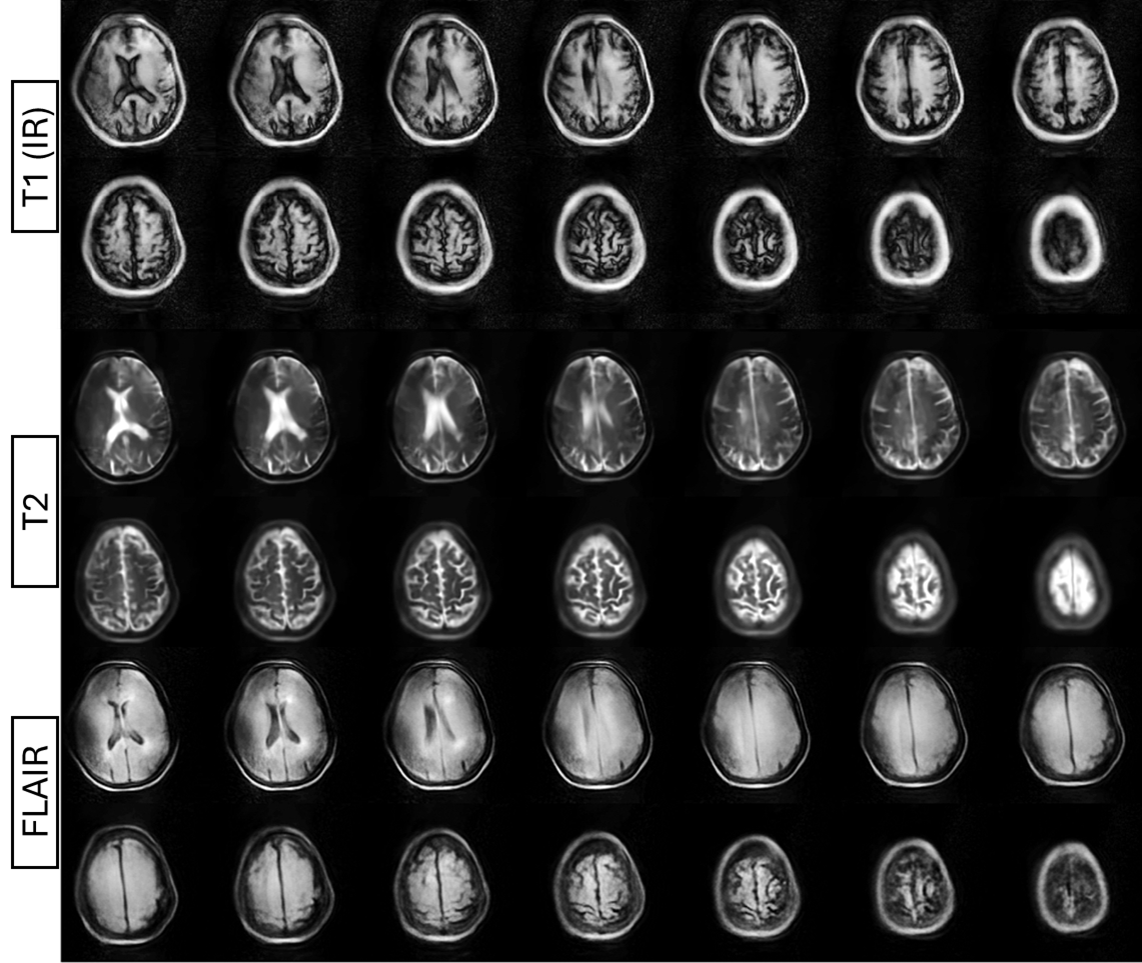

High Quality Images

Advanced technology delivers exceptional image clarity for accurate diagnosis from subtle injuries to complex anatomical structures, supporting precise clinical decision-making.

Imaging sequences include T1 RARE, T2 RARE, STIR RARE and RHO RARE all directed by a user interface. The equipment has a fully programmable Python environment.

A new generation of MRI scanners that operate with a low magnetic field (87 mT), are lightweight, portable and exploit efficient spatial coding schemes to enhance the diagnostic value of the resulting images, thus shifting the paradigm from highly sophisticated and expensive hardware to extremely efficient methods that balance rapidly growing healthcare costs worldwide. The elliptical bore of this new generation of MRI scanners allows imaging of the head and extremities.

Images made With Next MRI

With Next MRI you can investigate quickly and accurately, here we leave you some of the test images we have carried out.